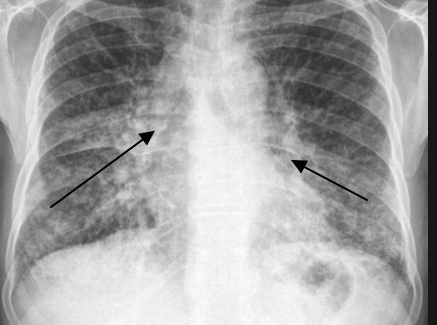

위 사진을 보면 양측의 허파문림프절 종대 양측 허파에서 입지모양의 음영이 확인되면 사르코이드증으로 진단을 내릴 수 있다. 이렇게 폐에 침범한 사르코이드는 바로 치료가 아닌 경과를 지켜보면서 치료 시기를 결정하게 된다.

만약 가역성 육아종일 경우 폐가 섬유화로 진행되어 폐 기능을 상실하기 전에 치료를 시작해야 하는데 상당히 어려운 타이밍입니다. 사이코이드의 대부분인 약 90% 이상은 폐 침범에 의해 생기는데 흡연 여부와 무관하게 발생한다.